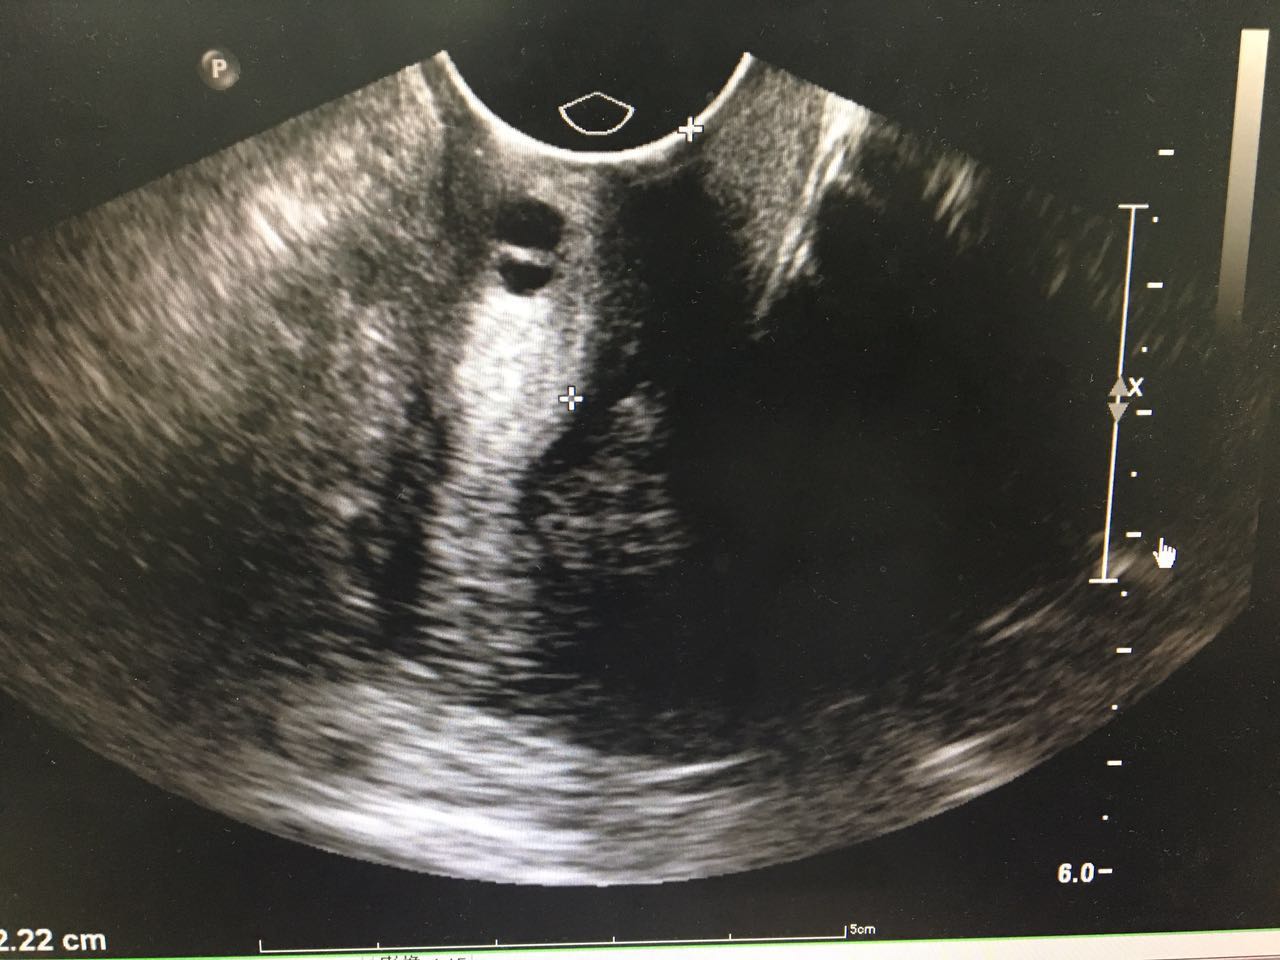

1、 患者女性,58岁  2、 主诉:发现盆腔肿物3月余;  3、 现病史:3-0-0-3,绝经2年。患者2015年体检未见明显异常,3月前体检时发现下腹部有一包块,无腹胀腹痛,无阴道出血,无阴道流液,无尿频尿急。查【妇科超声】示:左附件囊肿,卵巢囊腺瘤可能(子宫后上方无回声区116*94*110,形态规则,边界清晰,内壁光滑,后方回声增强,内见回声隔分隔成两房,隔上未见明显血流信号),【TCT】未见上皮内病变细胞或恶性细胞,肿瘤标志物检查未见异常。后行阴道镜检查示:宫颈转化区II型,宫颈活检病理报告:宫颈3、6、9、12点为黏膜慢性炎。现患者为求进一步诊治,门诊拟“左附件囊肿”收治入院。 自发病以来,患者精神可,一般情况可,睡眠可,胃纳可,二便基本正常。

4、妇科体检: 外阴(-);阴道畅;宫颈光,局部宫颈活检后改变;宫体:前位,偏向左侧,萎缩,表面光滑,活动可;子宫左上方可及囊性肿块直径8cm左右,质软,活动尚可,无压痛,右附件区未及明显异常。  5、辅助检查: 生化、血常规、阴道分泌物、内分泌检查未见异常 【TCT】:未见上皮内病变细胞或恶性细胞